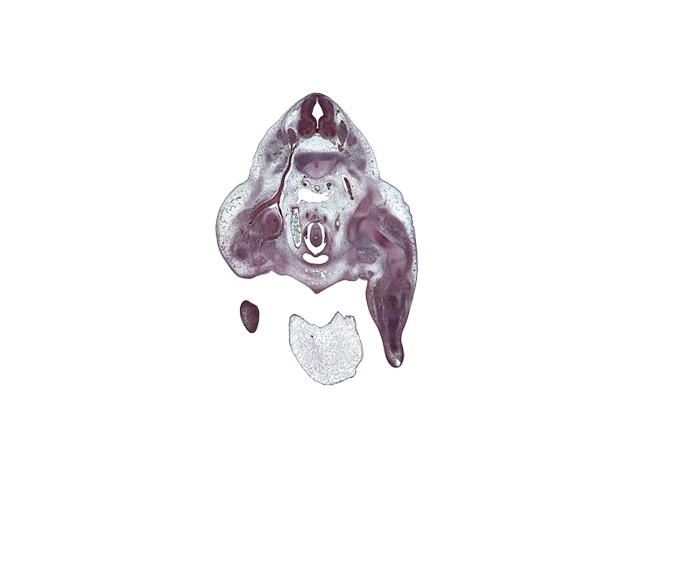

Carnegie Embryo #9325 | Location: 28-3-2

Keywords: L-3 / L-4 intervertebral disc, L-3 spinal ganglion, L-3 spinal nerve, L-4 ventral primary ramus, central canal, cephalic edge of lower limb, cephalic edge of phallus, femur, gubernaculum of gonad, hindgut, hip joint, ilium, inferior vena cava, internal iliac artery, ischium, labioscrotal swelling, median sacral artery, mesonephric duct, neural arch, notochord, osteogenic layer, peritoneal cavity, sympathetic trunk, umbilical cord, ureter, urinary bladder

Source: The Virtual Human Embryo.